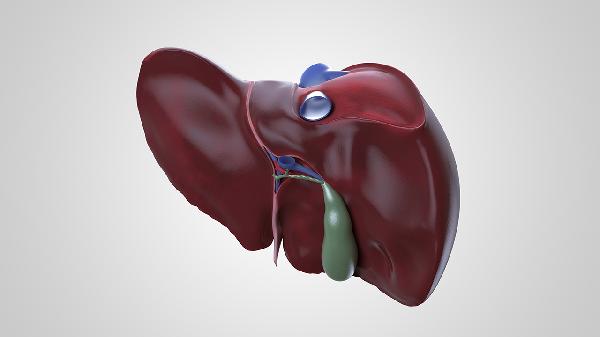

肝脏再生主要通过肝细胞增殖实现。当肝脏部分切除后,剩余肝细胞会迅速进入细胞周期,开始分裂和增殖。肝星状细胞和胆管细胞也参与这一过程,帮助重建肝脏结构和功能。再生过程中,肝脏会分泌多种生长因子和细胞因子,如肝细胞生长因子HGF和表皮生长因子EGF,这些物质促进细胞增殖和组织修复。